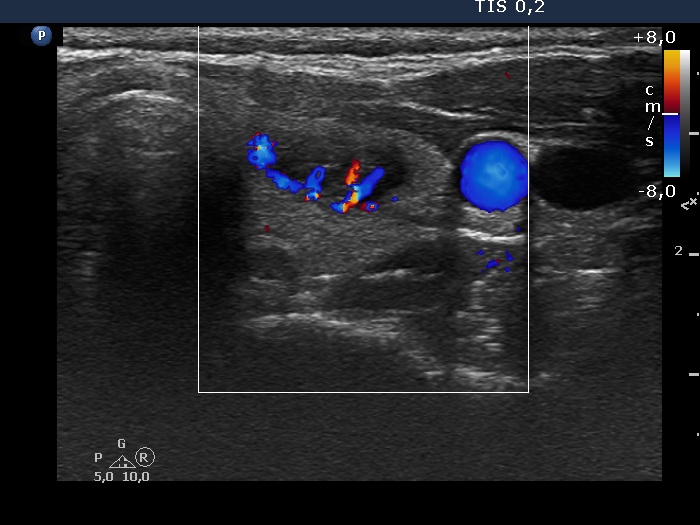

Right lobe, longitudinal scan

Left lobe, transverse scan, color Doppler mode - after aspirating 5 mL serous fluid. The intranodular vacularization is significantly increased.